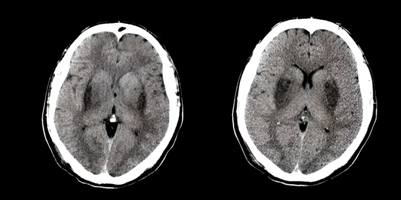

Ante la exploración física, el paciente se presentó afebril, taquipneico (45 rpm), con respiración de Kussmaul, saturación de oxígeno 98% al aire ambiente, y glucosa capilar 126 mg/dl. Al examen neurológico, presentaba somnolencia, desorientación en las tres esferas, pupilas isocóricas e hiporreactivas, reflejos de tronco encefálico conservados y mioclonías de moderada intensidad en miembros superiores. Los exámenes complementarios revelaron un hemograma normal, hiponatremia leve e hipokalemia (Na:133, K:2,62), cetonemia negativa, y acidosis metabólica con anión gap elevado (pH: 7.08). Referente a las imágenes, la tomografía axial computarizada (TAC) simple de cerebro reveló hipodensidad bilateral a nivel putaminal, compatible con intoxicación por metanol. (Figura 1).

Figura 1 Paciente con necrosis características de la intoxicación por metanol. Tomografía simple de cerebro en corte axial, que muestra hipodensidades bilaterales en ganglios de la base de forma predominante en los putamen.

-TAC: necrosis bilateral de GB, compromiso selectivo o predominante del putamen con integridad del globo pálido (Figura 1), hipoatenuación de la sustancia blanca y hemorragia cerebral e intraventricular. (1)(3)